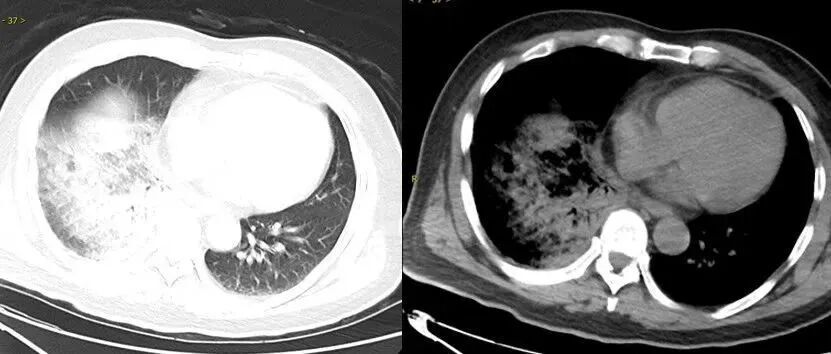

△鹦鹉热衣原体肺炎影像示例

图源:健康广东